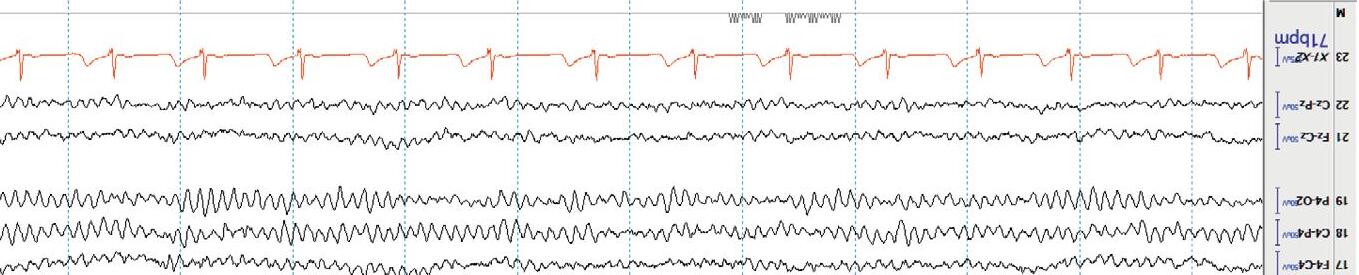

Awake Lookforthe alpharhythm(posteriordominantrhythm,PDR).Thisisthe 8.5 – 13Hz(alpharange)rhythm,maximalintheposteriorheadregions, thatattenuateswitheyeopening(anindicationofreactivity).Thealpha rhythmisanobviousfeatureofnormalwakefulnessandisbestobserved aftereyeclosureintheoccipitalchannels(O).Loweramplitude beta activity occursanteriorly.Anyintrusionofthetaordeltaactivityduringfull wakefulnessisusuallyindicativeof anabnormality.Furthermore,theamplitudeofthebackgroundactivityshouldnormallydecreasefromposterior (O)toanterior(Fp).Thisiscalledthenormal anterior –posterior(AP) gradient .Additionally,therewillbeartifactfrom eyeblinks and muscle activityinthefrontalisandtemporalismuscles. Figure1.6 showsanEEG duringnormalwakefulness.

Figure1.6 NormalawakeEEG;thePDRishighlightedinred.